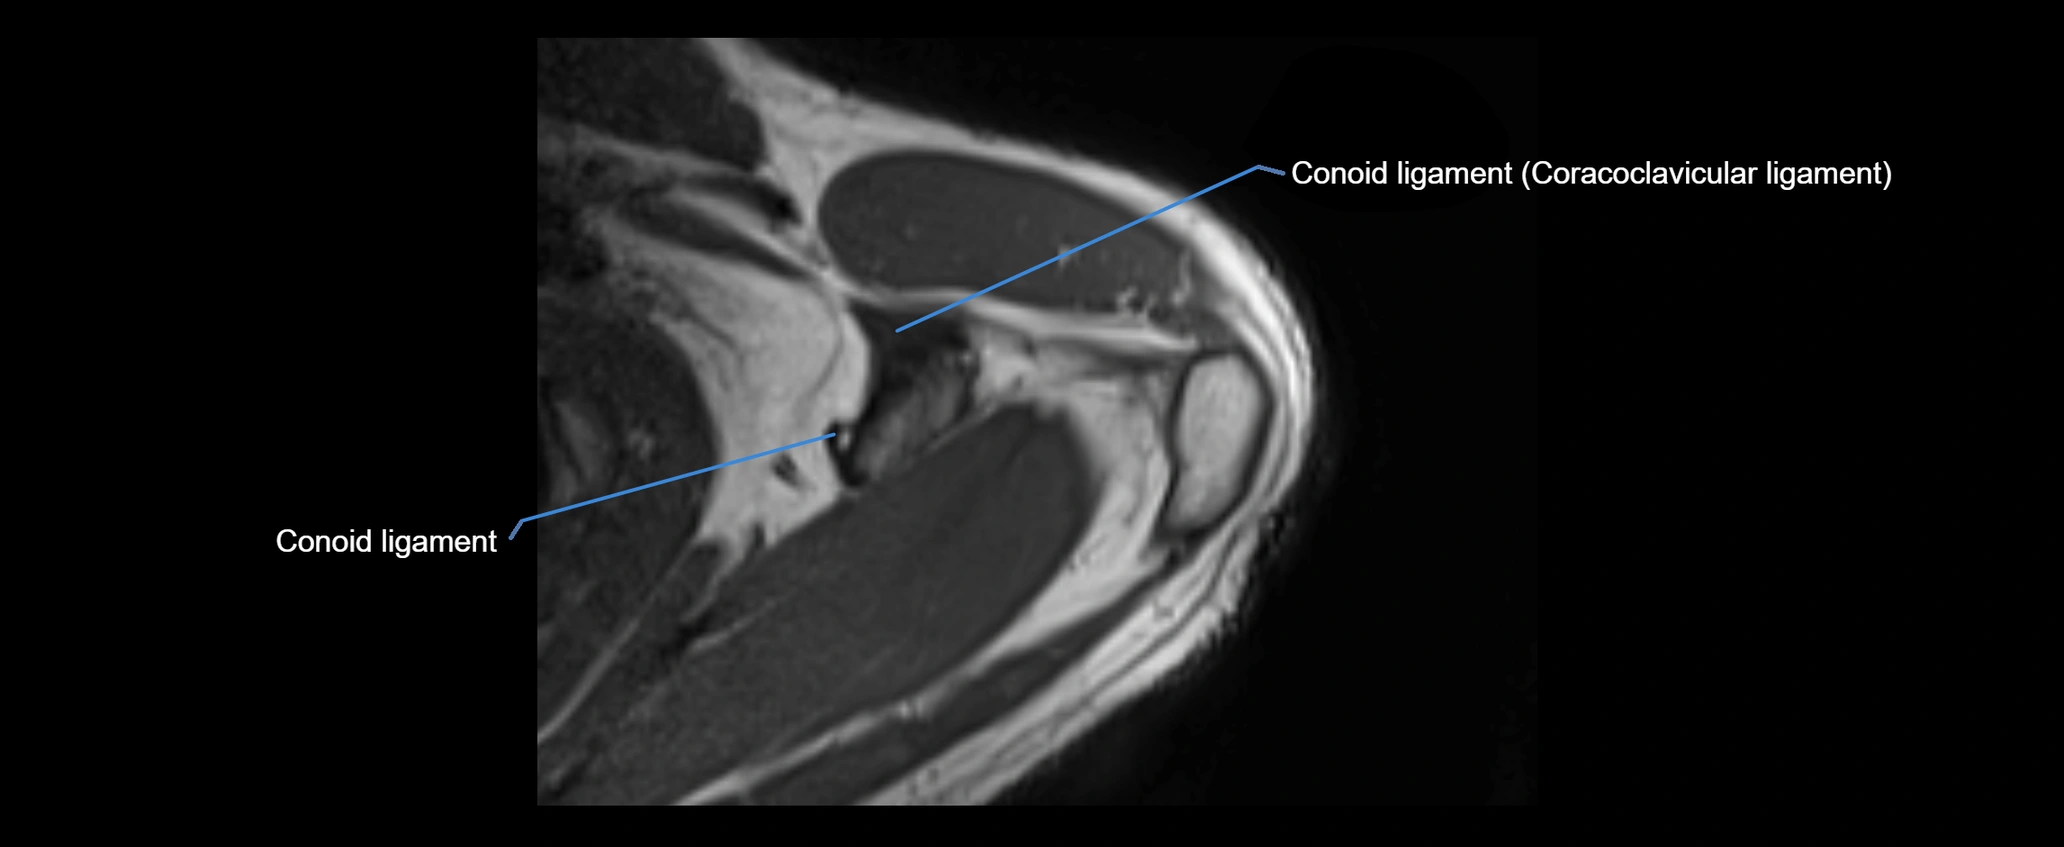

MRI images

image